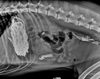

For the past 8 years, Veterinary Practice News has had an annual x-ray contest for the craziest things pet's have eaten. Here are the winners for 2013.